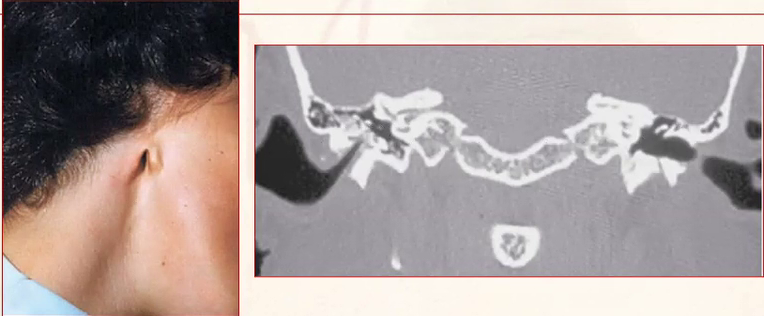

• Também chamados de Coloboma Auris ou Sinus pré-timpânico.

• Fusão incompleta dos 6 botões óticos que formarão opavilhão da orelha.

• Origem: 1° e 2° arcos branquiais.

• A localização das fístulas geralmente são na margem ascendente da hélice.

• Trajeto costuma ser tortuoso, com prolongamentos (igual raízes de uma árvore).

• A principal indicação cirúrgica é infecção de repetição (pode ser utilizado azul de metileno para marcação, incisão em meia lua a partir do arco zigomático anterior à fístula até terço superior da mastoide, com remoção tomando cuidado com nervo facial).

• A simples drenagem não resolve e é a principal causa de recidivas infecciosas.